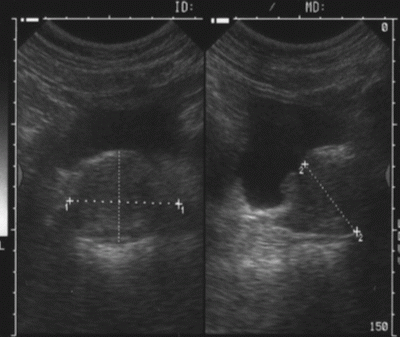

El ultrasonido de próstata proporciona imágenes de esta glándula del hombre.

Ecografía abdominal, para la cual hay que beber líquido antes y se realiza a traés del abdomen, solicitada de rutina por el urólogo; y

Ecografía transrectal, la cual normalmente requiere inserción de una sonda de ultrasonido en el recto del paciente. La sonda envía y recibe ondas de sonido a través de la pared del recto hasta dentro de la próstata que se encuentra delante del recto. Esta ecograía esta limitada para estudios clínicos y en los casos de ser necesaria uan biopsia prostática.